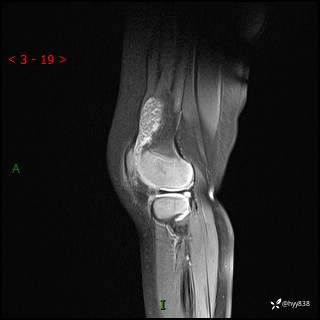

现病史:患儿1月前无明显诱因出现左下肢跛行,伴左膝关节红肿,无发热、咳嗽、恶心、呕吐等症,于当地医院就诊行X线片未提示异常,今至我院门诊就诊,门诊医师拟“跛行待查”收入院。 病后,患儿精神、食欲可,睡眠欠安,大小便通畅,体力体重无明显下降。

左膝MRI平扫